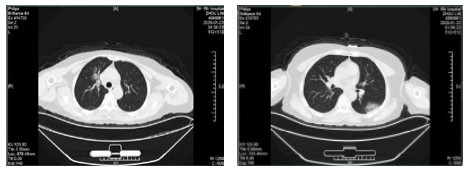

| 图 1 病例1,男性,65岁,沪籍,否认武汉流行病学接触史,发病前2周内每天有大型医院陪护史及疲劳史,既往体健,发热1 d入院,体温38.5℃,无咳嗽症状,无鼻塞,流涕,血白细胞总数及淋巴计数正常,甲乙型流感病毒筛查阴性,新型冠状病毒核酸检测阳性。肺部CT提示双肺多发磨玻璃结节,病灶贴近胸膜,局部小叶间隔增厚,炎症沿支气管血管走向分布,散在小结节影及纤维条索影 Fig 1 Case 1, male, 65 years old, born in Shanghai, denied the history of epidemic exposure of Wuhan. He had a history of accompanying in hospital every day and fatigue in the first two weeks before the onset of the disease. He was hospitalized one day after the onset of fever, with a body temperature of 38.5 ℃, no cough, no nasal obstruction and runny nose, normal WBC and lymph count, negative influenza A and B virus screening, and positive novel coronavirus nucleic acid test. Lung CT showed multiple ground glass nodules in both lungs. The focus was close to pleura, the interlobular septum was thickened, the inflammation distributed along the direction of bronchi and blood vessels, scattered in small nodule shadow and fibrous cord shadow |